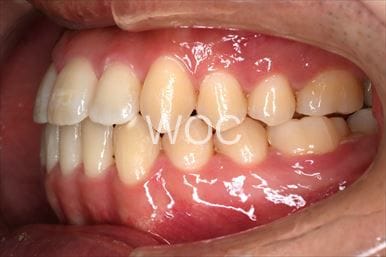

治療後1

治療後2

治療後3

治療後4

治療後5

- 年齢:20歳女性

- 主訴:出っ歯が気になる

- 基本矯正料金:120万円

- 治療期間:1年7ヶ月

- 抜歯部位:上顎両側第一小臼歯